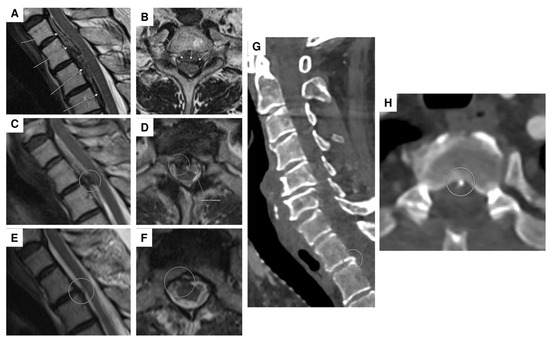

| 2 | F | 69 | headaches and abdominal complaints | oriented 3×, marked meningism, positive Lasègue sign | spinal SAH with (partial) thrombosed intraspinal aneurysm at T2 | aneurysm | multiple DSA, multiple spinal MRI | surgical procedure (resection of the aneurysm) |